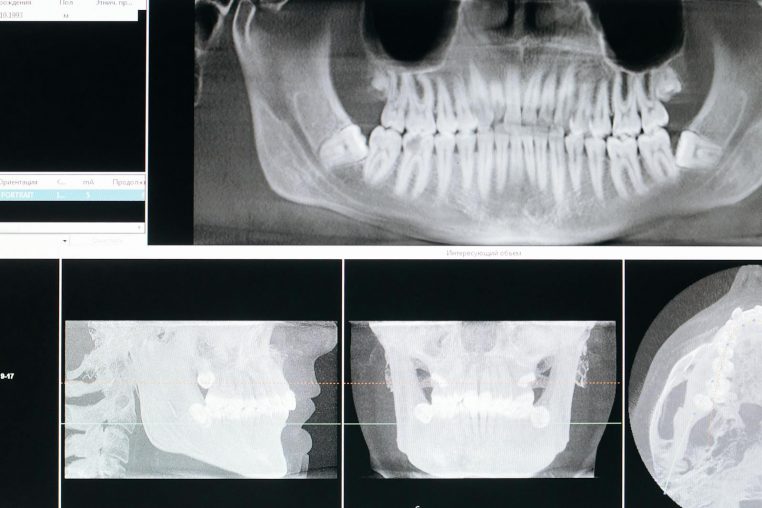

« L’orthodontiste est entré dans la salle et a affiché les radios sur l’écran », raconte la maman à Newsweek. « Nous les avons vues en même temps et pendant plusieurs minutes, nous avons essayé de comprendre ce que nous étions en train d’observer. »

Sur l’image, un petit objet métallique apparaissait, coincé dans les sinus de la fillette. La mère était stupéfaite et n’avait aucune idée de ce que cela pouvait être. Mais une personne dans la pièce savait exactement ce qu’il s’était passé : sa fille.